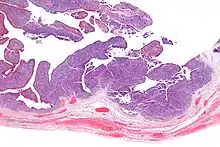

| Micrograph of transitional cell carcinoma of the ovary. H&E stain. |

Transitional cell carcinoma of the ovary (TCC of the ovary) is a rare type of ovarian cancer that has an appearance similar to urothelial carcinoma (also known as transitional cell carcinoma).[1]

TCC of the ovary is diagnosed by examination of the tissue by a pathologist. It has a characteristic appearance under the microscope and distinctive pattern of immunostaining.[2]

Low mag.